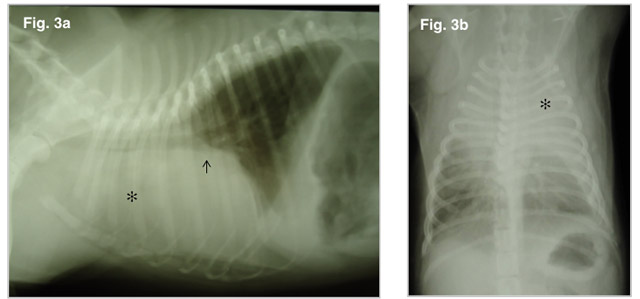

Facilmente curabile Tipi A seconda della quantità. Dato dallo spostamento del polmone verso la parete toracica durante l'inspirazione (Fig 3) Prevenire il cancro ai polmoni solo se il fumo. Di respirare in modo.